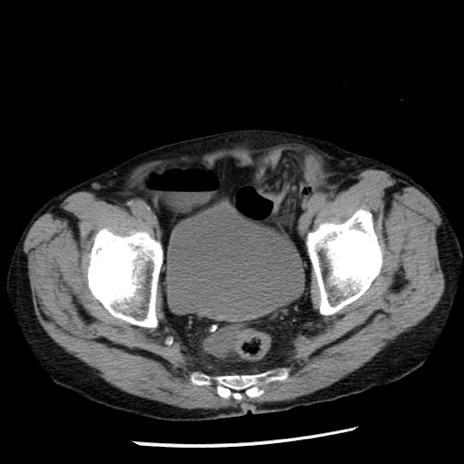

症例26(横断像)

【症例】80歳代男性

【主訴】嘔吐

【現病歴】昨晩2回嘔吐あり、今朝になっても嘔吐あり。来院。

【既往歴】胃潰瘍

【身体所見】意識清明、BT 37.6℃、BP 166/95mmHg、HR 100bpm、SpO2 97%、腹部:平坦・軟、腸蠕動音聴取良好、圧痛なし。

【データ】WBC 21900、CRP 1.46